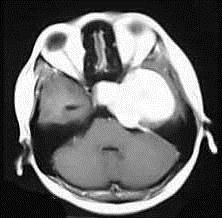

问题 女,36岁,抽搐半年,近10余天头痛加重,磁共振检查如图,选择最可能的诊断()

选项 A.胶质瘤 B.脑膜瘤 C.动静脉畸形 D.海绵状血管瘤 E.蛛网膜囊肿

答案 B